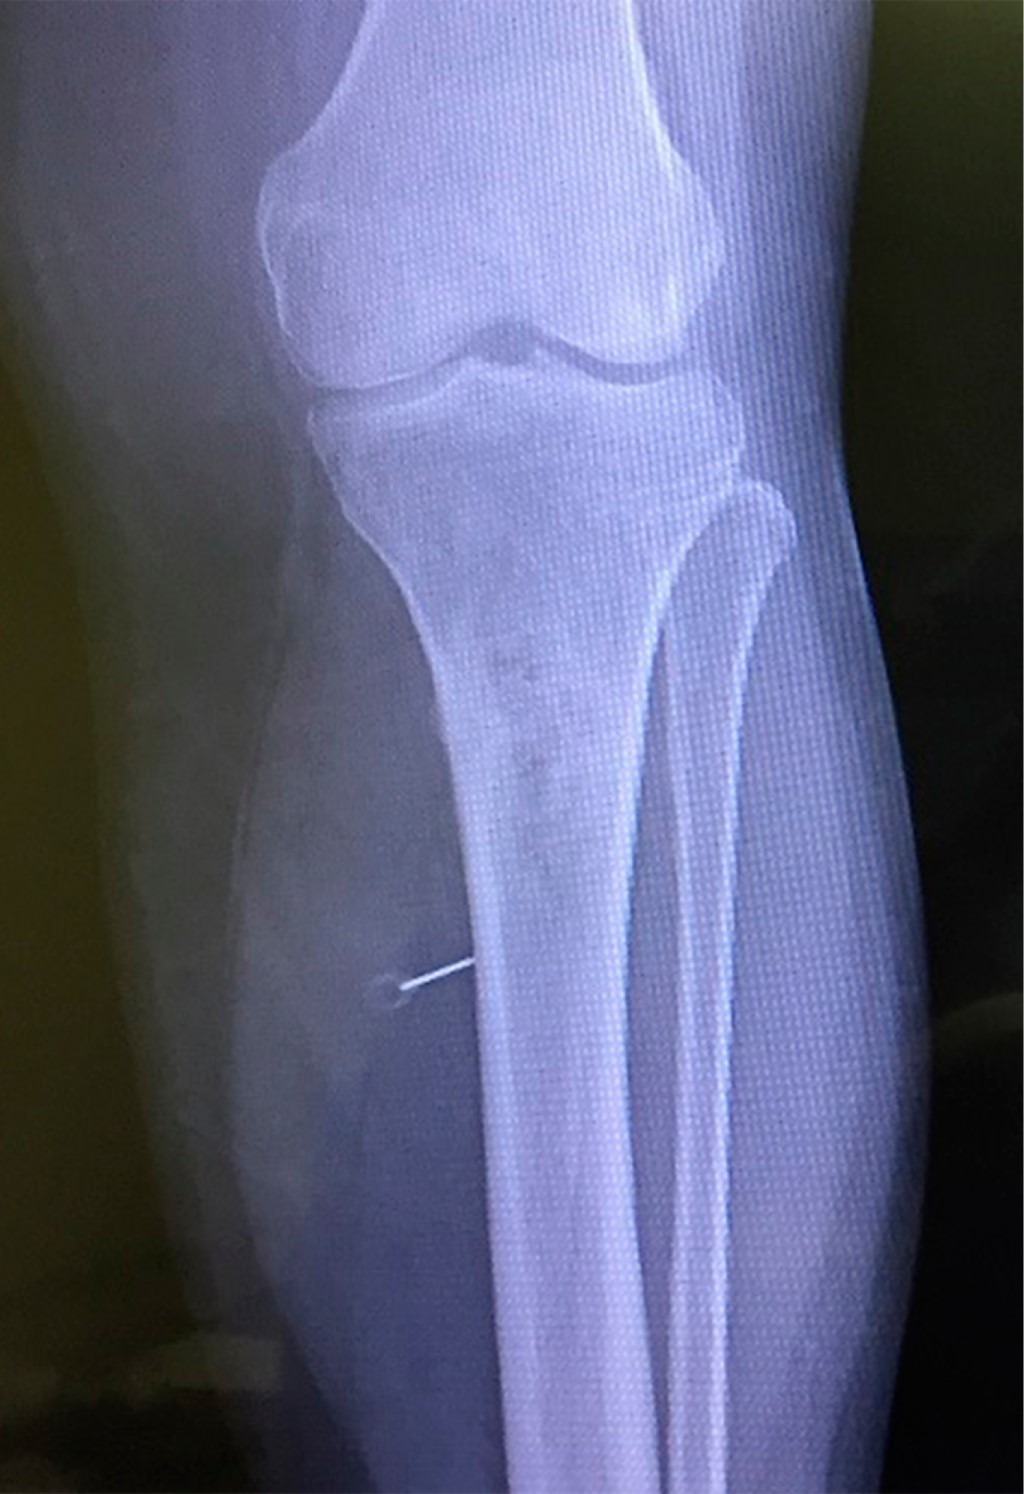

Femenino de 55 años, sin antecedentes de importancia, quien inició seis meses previos a ser evaluada, con dolor en tercio superior de pierna izquierda a 2 cm por debajo de tuberosidad tibial, siendo de mayor intensidad durante la ambulación, el cual disminuía con uso de paracetamol. Acude a consulta por notar aumento de volumen en dicha zona, se solicitaron estudios de imagen, los cuales revelaron tumor en tercio proximal de la tibia. Se le hospitalizó para realizar estudios con el fin de complementar el diagnóstico, las radiografías mostraron lesión de carácter blástico en tercio superior de tibia izquierda (Figura 1), la biopsia confirmó osteosarcoma. Los estudios de laboratorio con resultados normales para citometría hemática, pruebas de funcionamiento hepático, electrólitos y función renal, sólo discreta elevación de deshidrogenasa láctica (340 UI/L) y de fosfatasa alcalina (155 UI/L). Se efectuó tomografía computarizada de tórax con resultados normales, tomografía computarizada y resonancia magnética para planeación quirúrgica así como centellograma óseo corporal total (tecnecio) encontrando sólo afección de tibia izquierda. Se le estadificó como osteosarcoma central convencional intramedular de alto grado de tipo osteoblástico en etapa IIA, T2, N0, M0. La paciente se sometió a resección de la tibia proximal (Figura 2), su reconstrucción con endoprótesis (prótesis tumoral OSS, Stryker. USA) y el mecanismo extensor de rodilla con colgajo de gastrocnemio y cierre de piel utilizando injerto de mediano grosor de piel de muslo ipsilateral (Figuras 3 y 4). Su evolución postoperatoria fue satisfactoria (Figura 5), se refirió a rehabilitación, logrando a los tres meses: flexoextensión activa de rodilla de 0 a 65o, con fuerza muscular de 4 en escala de Daniels para cuádriceps izquierdo y 5/5 para resto de músculos ipsilaterales y contralaterales; no presentó anormalidades en la sensibilidad, y con llenado capilar normal, con independencia en todas las ADVH. Se anota que fue canalizada a oncología médica desde una semana previa a la cirugía continuando actualmente su control con ifosfamide-etoposide.

Figura 1